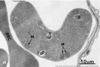

What does Sudan Black “B” show?

Lipid droplets, lysosomes, and mitochondria